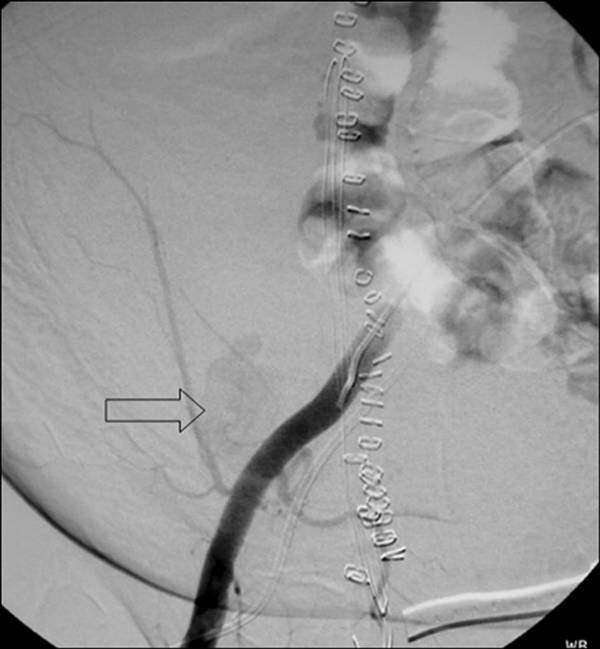

Coil Embolization Pseudoaneurysm .   facing a dilemma in the treatment of an internal mammary artery mycotic pseudoaneurysm: (2) at the site of native artery and synthetic graft.   (b) digital subtraction aortogram image demonstrates successful embolization of the pseudoaneurysm.   successful coil embolization of a large anterior tibial artery pseudoaneurysm after.   psas may occur under 4 circumstances: (1) after catheterization (figure 2);   a total of 12 detachable microcoils (pc 400 coil®; Penumbra, alameda, ca, usa) were used for embolization of the pseudoaneurysm,.   embolization of the pseudoaneurysm itself by coils is achieved by advancing a catheter into the sac.

embolization of the pseudoaneurysm itself by coils is achieved by advancing a catheter into the sac. Penumbra, alameda, ca, usa) were used for embolization of the pseudoaneurysm,.   facing a dilemma in the treatment of an internal mammary artery mycotic pseudoaneurysm: (1) after catheterization (figure 2);   successful coil embolization of a large anterior tibial artery pseudoaneurysm after.   psas may occur under 4 circumstances:   a total of 12 detachable microcoils (pc 400 coil®;   (b) digital subtraction aortogram image demonstrates successful embolization of the pseudoaneurysm. (2) at the site of native artery and synthetic graft.